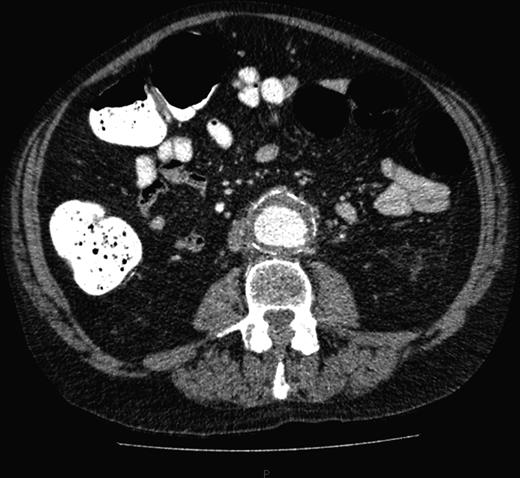

A computed tomography (CT) of the abdomen and pelvis was performed. This showed a grossly distended urinary bladder and compression of the sigmoid colon against the sacral promontory causing bowel obstruction (Figs 1 and 2, respectively) as well as a 4.9 cm abdominal aortic aneurysm without any signs of a rupture (Fig. 3). The plan was to consult our vascular colleagues regarding management of the AAA once the obstruction had settled.

The initial CT scan of the abdomen showing a large distended bladder.